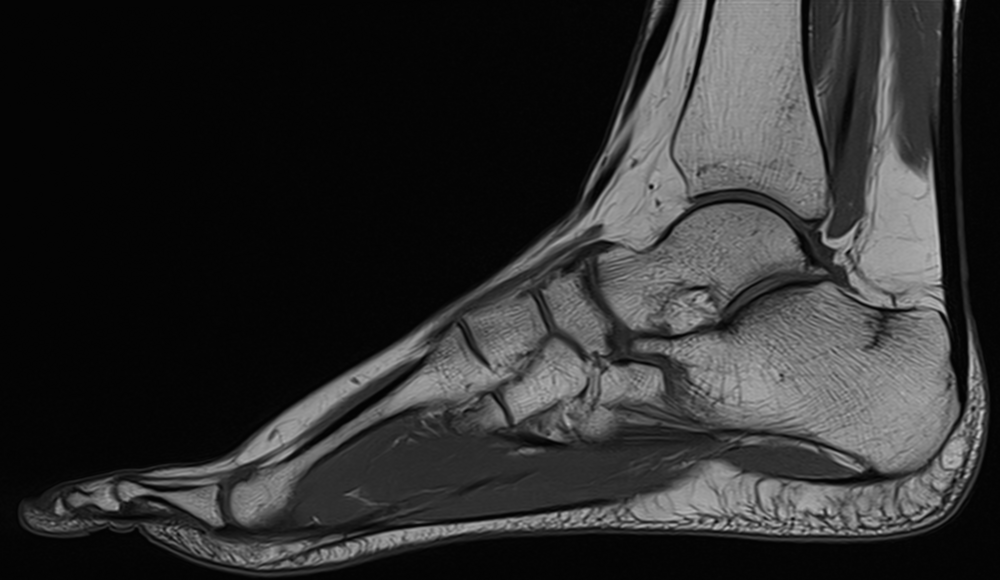

MRT-Diagnostik bei Sport- und Arbeitsunfällen

In unserer Praxis für Radiologie in Löbau bieten wir die MRT-Diagnostik nach Sport- und Arbeitsunfällen als diagnostisches Verfahren an, um Arbeits- oder Sportverletzungen zu untersuchen. Dabei arbeiten wir mit regionalen Sportvereinen zusammen. Die MRT liefert Ihrem Arzt wertvolle Informationen, um eine individualisierte Behandlungsstrategie zu entwickeln, die auf Ihre spezifischen Bedürfnisse zugeschnitten ist. Durch ihre präzise Darstellung von Muskeln, Sehnen, Bändern, Knochen und anderen Geweben ermöglicht sie es, Verletzungen und Schäden detailliert zu beurteilen. So können etwa Knochenbrüche, Bänderrisse, Muskelzerrungen oder Gelenkschäden sichtbar gemacht werden. Ihr behandelnder Arzt kann mithilfe der MRT-Diagnose die Behandlung frühzeitig und gezielt planen und so die Weichen für eine schnelle Genesung stellen.